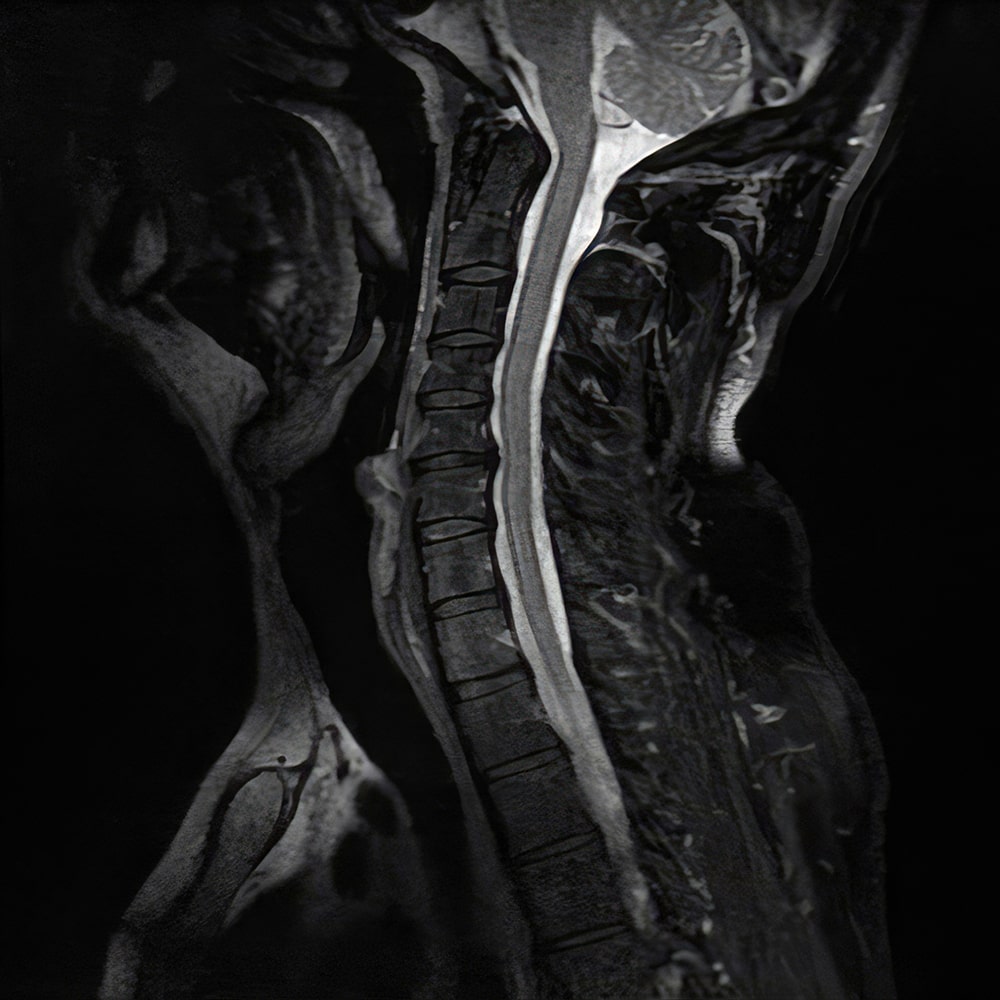

Non-surgical decompression for disc-related pain relief.

DTS therapy for managing degenerative disc disease.